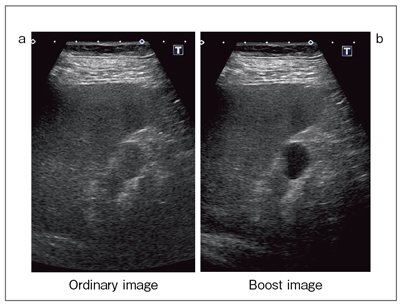

もうひとつの超音波の「視点を変える」方法として,東芝メディカルシステムズと開発中の,高分解能で高ペネトレーション画像を実現する“Boost Image(仮称)”について臨床画像を紹介する。

図8 aは,従来のAplioの7MHzリニアプローブで撮像した脾動脈瘤だが,アーチファクトや減衰があることがわかる。これをBoost Image(図8 b)で見ると,横隔膜のラインもきれいに描出され,浅部から深部まで高分解能のままでペネトレーションがとれていることがわかる。また,正常な膀胱-前立腺-直腸の画像(図9)では,非常に深く見にくい直腸の層構造が,Boost Imageでは明瞭化している。超音波による消化管検査を行う場合,深部の直腸の評価には難渋するが,その意味でもBoost Imageへの期待は大きい。

肝細胞がん(HCC)では,通常の画像では減衰が強く,肝内の腫瘍の存在は明らかでない(図10 a)。Boost Image(図10 b)で見ると,全体像が把握でき,内部性状も明瞭に描出される。

Boost Imageは,画像上の効果としては分解能が高くペネトレーションが良いということで,ある意味では超音波にかかわるものが夢に描いていた画像だと言える。Boost Imageでは,S/N比も向上しコントラストの改善も図れる。